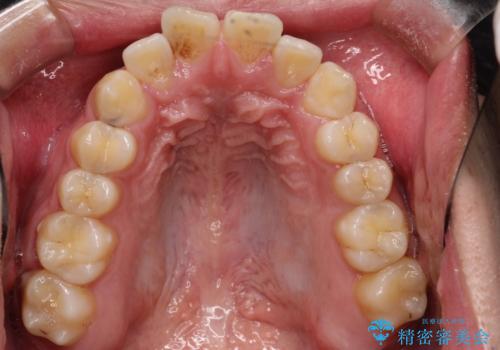

【ワイヤー矯正】前歯の凸凹を治したい。

- 前歯の凸凹を主訴に来院されました。

患者様がマウスピース矯正の使用時間に不安があるため、ワイヤー矯正にて治療を行なっております。